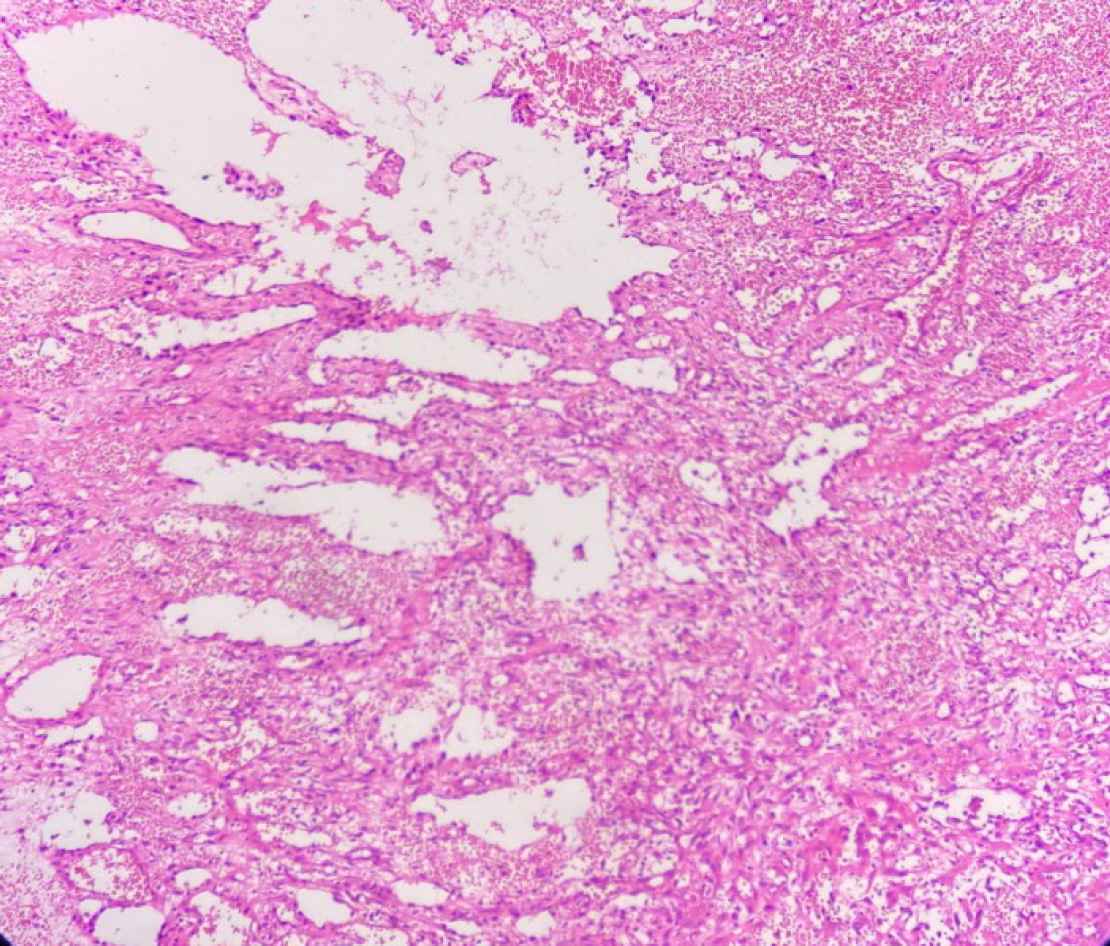

Macroscopically, the specimen was a 5× 2.5× 2 cm soft brown tissue with no identifiable mass lesion. Histopathologic examination showed polygonal cells and some spindle-shaped cells arranged around the intercommunication blood vessels. The solid areas of epithelioid anaplastic cells with large pleomorphic, vesiculated nuclei, prominent nucleoli and abundant mitotic activity were present (Figures 1 and 2). The vascular channels were lined by atypical spindle to plump cells. Some foci of hemorrhage and necrosis were also observed. Through immunohistochemical analysis, neoplastic cells demonstrated intense positive reactivity for CD31 and vimentin. Ki67proliferative index was 20% (Figure 3). A positive cytoplasmic immunoreactivity in tumor cells for WT1 was detected. Reactive mesothelial cells revealed positive nuclear staining for later marker in the same sections. Hence, the overall findings were consistent with pericardial angiosarcoma, epithelioid variant. After the operation, the patient received three cycles of chemotherapy with adriamycin, ifosfamide, and mesna. Unfortunately, she finally died of multiple pleural metastases and progressive cardiac invasion less than three months following the operation.

Fig. 1.H&E stain (Objective 10x). Irregular blood vessels are surrounded by neoplastic cells in two different patterns: spindle cells fusing with each other and cells forming nests